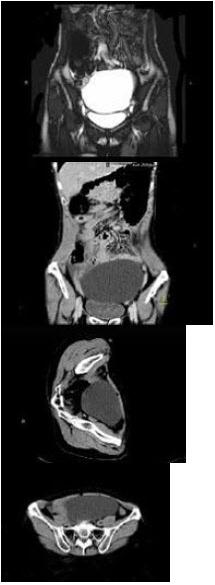

- 单项选择题 女,62岁,左下腹持续性疼痛3天,伴恶心、呕吐,左侧附件区扪及一囊性包块,活动表面光滑,压痛明显,CT和MRI检查如图所示,下列说法错误的是()。

A、左侧附件区一囊性占位性病变

B、该病灶包膜完整,边界清晰

C、膀胱向下受压移位

D、卵巢囊肿扭转

E、卵巢囊腺瘤

- E